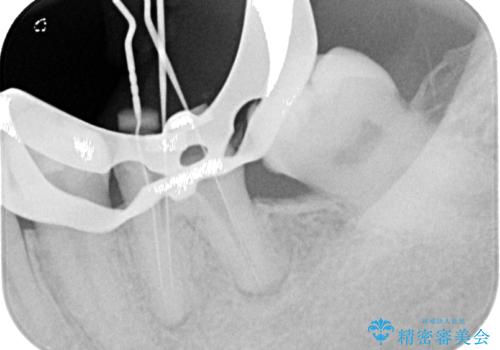

下顎大臼歯の再根管治療とオールセラミッククラウンによる補綴治療

噛んだ時に少し違和感があり、レントゲン上で根尖病変が確認できるため再根管治療を行いました。

根管治療後は、ファイバーコアによる土台と、オールセラミッククラウンによる補綴治療を行いました。